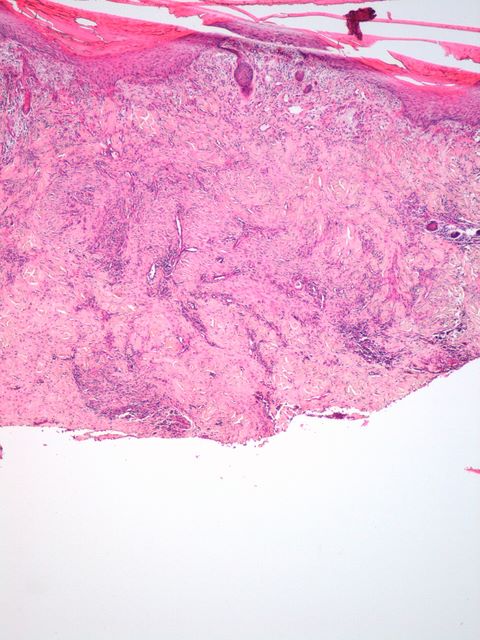

806 -- image_2009y11m15d_07h40m50s.jpg